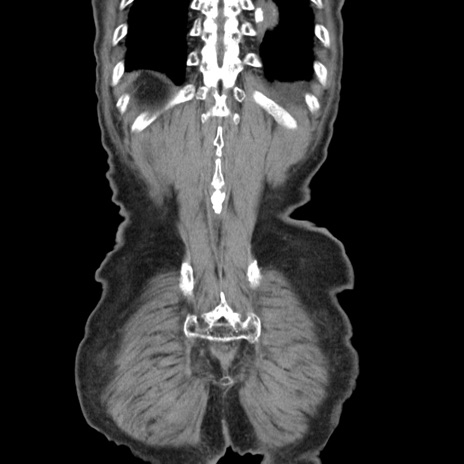

矢状断像